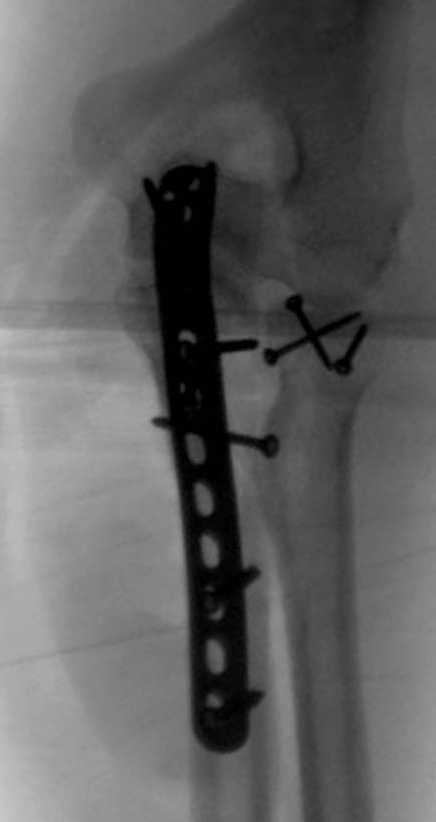

Для фиксации перелома локтевого отростка на сегодня множество преконтурных с блокирующими возможностями пластин.

Стабильную фиксацию, особенно при оскольчатых

переломах, можно добиться, применяя технику Bridge Plate, и за счет тех пластин, где имеется возможность проведения множественных шурупов (2.7 мм) проксимально.

Здесь выставлены несколько случаев и варианты фиксации локтевого отростка, некоторые в комбинации с другими переломами.

1 вариант применен ACUMED локинг пластина